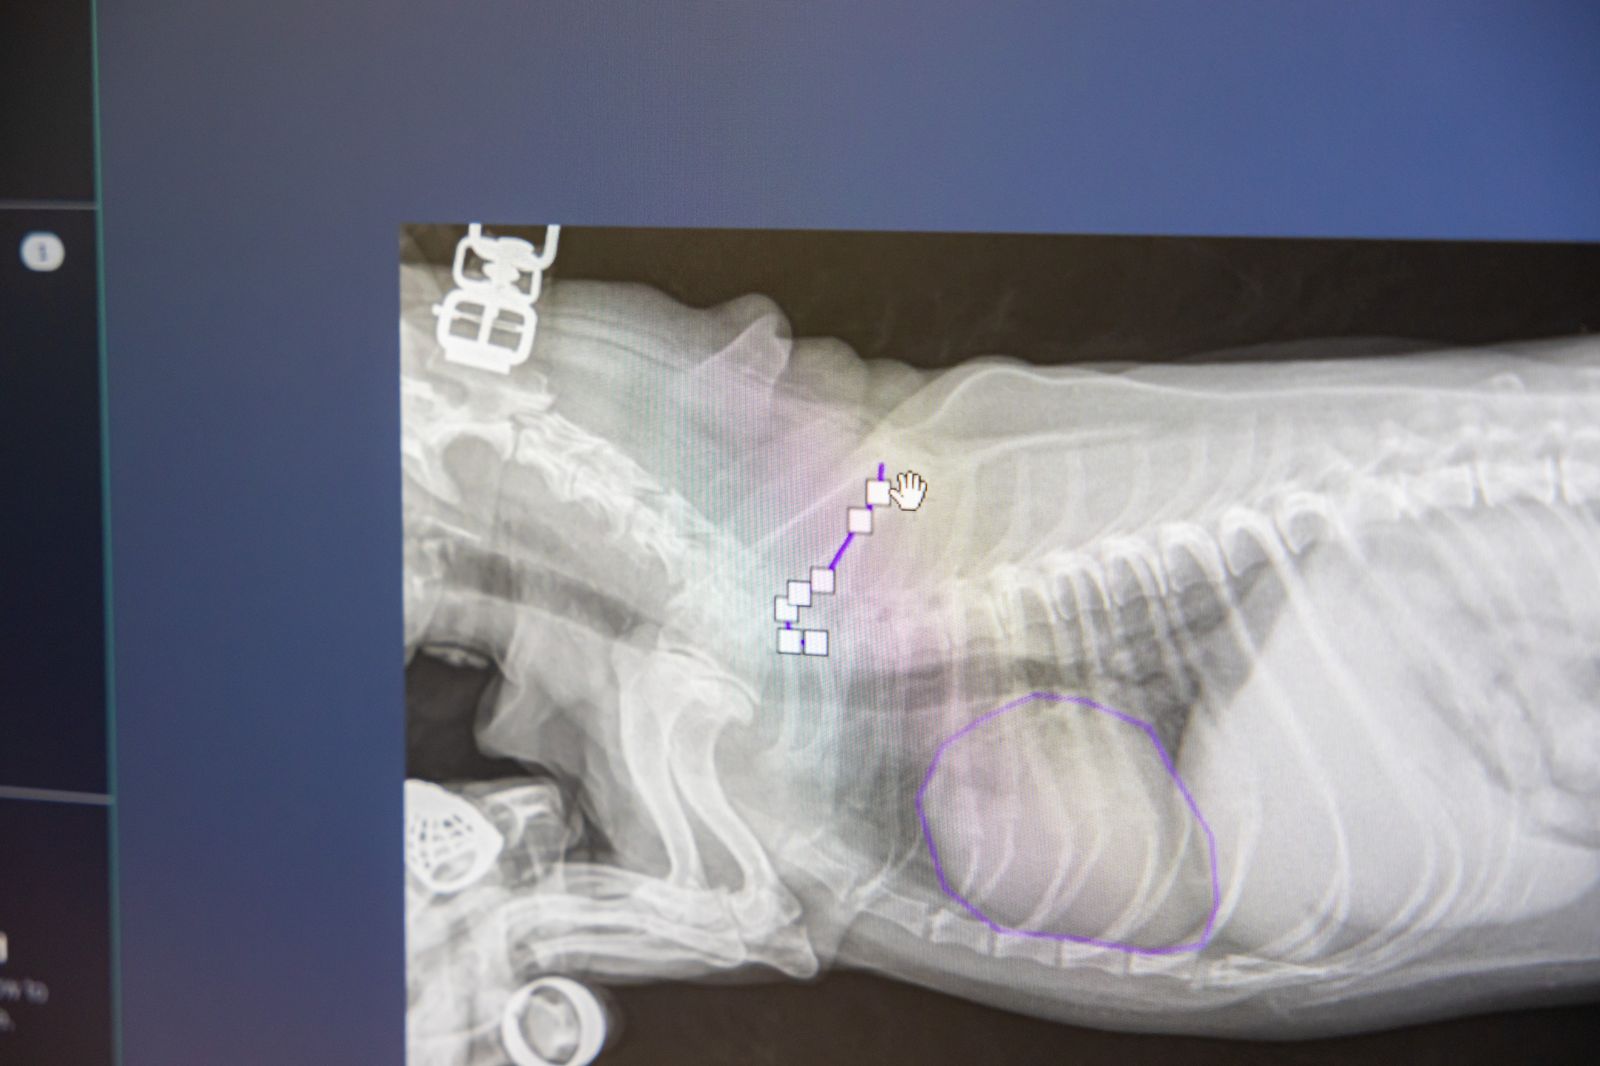

После совещания была организована экскурсия по лабораториям и подразделениям университета, работающим в сфере искусственного интеллекта и цифровой трансформации АПК на которой гостям были представлены ключевые разработки университета в области ИИ для сельского хозяйства, а также проекты студентов и молодых исследователей. Представленные решения охватывают широкий спектр задач — от анализа больших массивов отраслевых данных и прогнозирования урожайности до использования методов биоинформатики и интеллектуальной обработки изображений в растениеводстве и животноводстве.